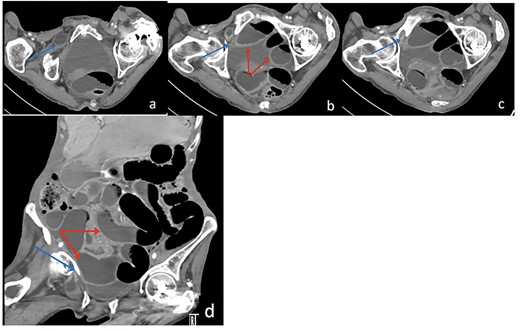

The patient’s lab results revealed leukocytosis of (12.40 m/mm3), and C-reactive protein of (28 mg/l). Abdominal X-ray demonstrated distended small bowel loops with multiple air fluid levels (Fig. 1). Moreover, CT revealed right sided obturator foramen hernia containing a segment of distal ileum causing high-grade small bowel obstruction, which reached up to 4 cm (Fig. 2). The CT also showed extensive bronchiectasis and consolidation with mucus plugging in the lung base.

Axial (a–c) and Coronal (d) contrast-enhanced reformatted CT image of the abdomen shows distal ileal loop segment protrudes through the right obturator foramen with the herniated segment trapped between the right obturator externus and pectineus muscles (blue arrow), there is proximal upstream dilated small bowel loops (red arrows). In keeping with high-grade small bowel obstruction due to strangulated obturator hernia.